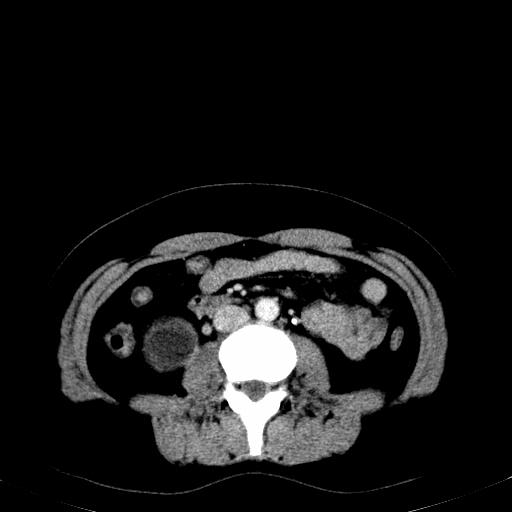

患者体检发现右肾体积增大,怀疑右肾积水

右肾多发囊肿,左肾、左输尿管结石

右肾重度积水,以肾盏积水明显,有分隔,上段输尿管轻度扩张,管壁增厚,考虑肾结核可能,请结合尿检查,胸部拍片排除肺结核。

右侧肾积水、左侧肾结石

右侧肾积水、左侧肾结石  ,要排除右肾结核可能。

右肾重度积水,建议ct向下扫描或逆行造影,左肾及左输尿管结石 .

右侧肾积水、左侧肾结石 ,原因待查

患者尿常规正常,b超未发现明显结石,自身也无明显感觉异常。

请问多囊肾与肾积水怎么鉴别